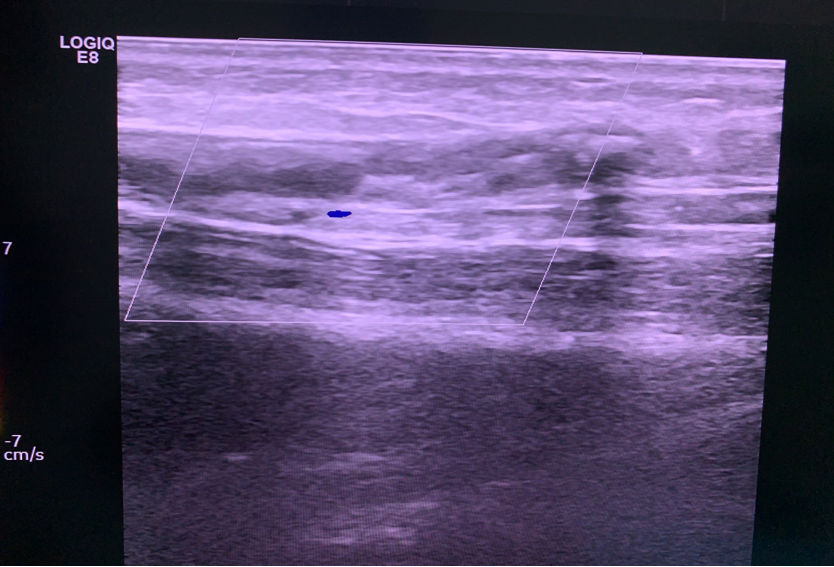

国内首例MOCA手术

2025年8月8日,浙江省人民医院完成了我国第一例MOCA手术。患者为90余岁高龄,心脏功能差,大隐静脉主干表浅,不适合热消融。术中通过4F鞘高速旋转破坏内膜后注入硬化剂,效果理想。